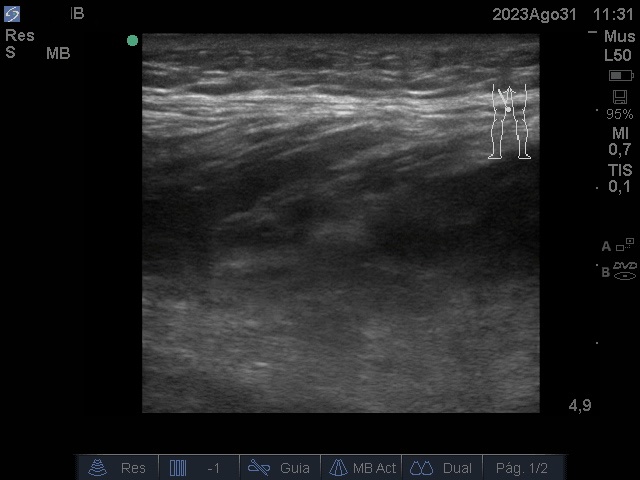

Ecografía: discontinuidad de la disposición de las fibras musculares normales a nivel del tercio medio de los cuerpos musculares isquiosurales que afecta al músculo semitendinoso del miembro ingerior izquierdo, edema focal e imágenes.

Anecogénicas intramusculares, sin captación doppler.

Se observa imagen anecoica irregular, elipsoide que se interpreta como sangrado entre el músculo semitendinoso y semimembranoso.